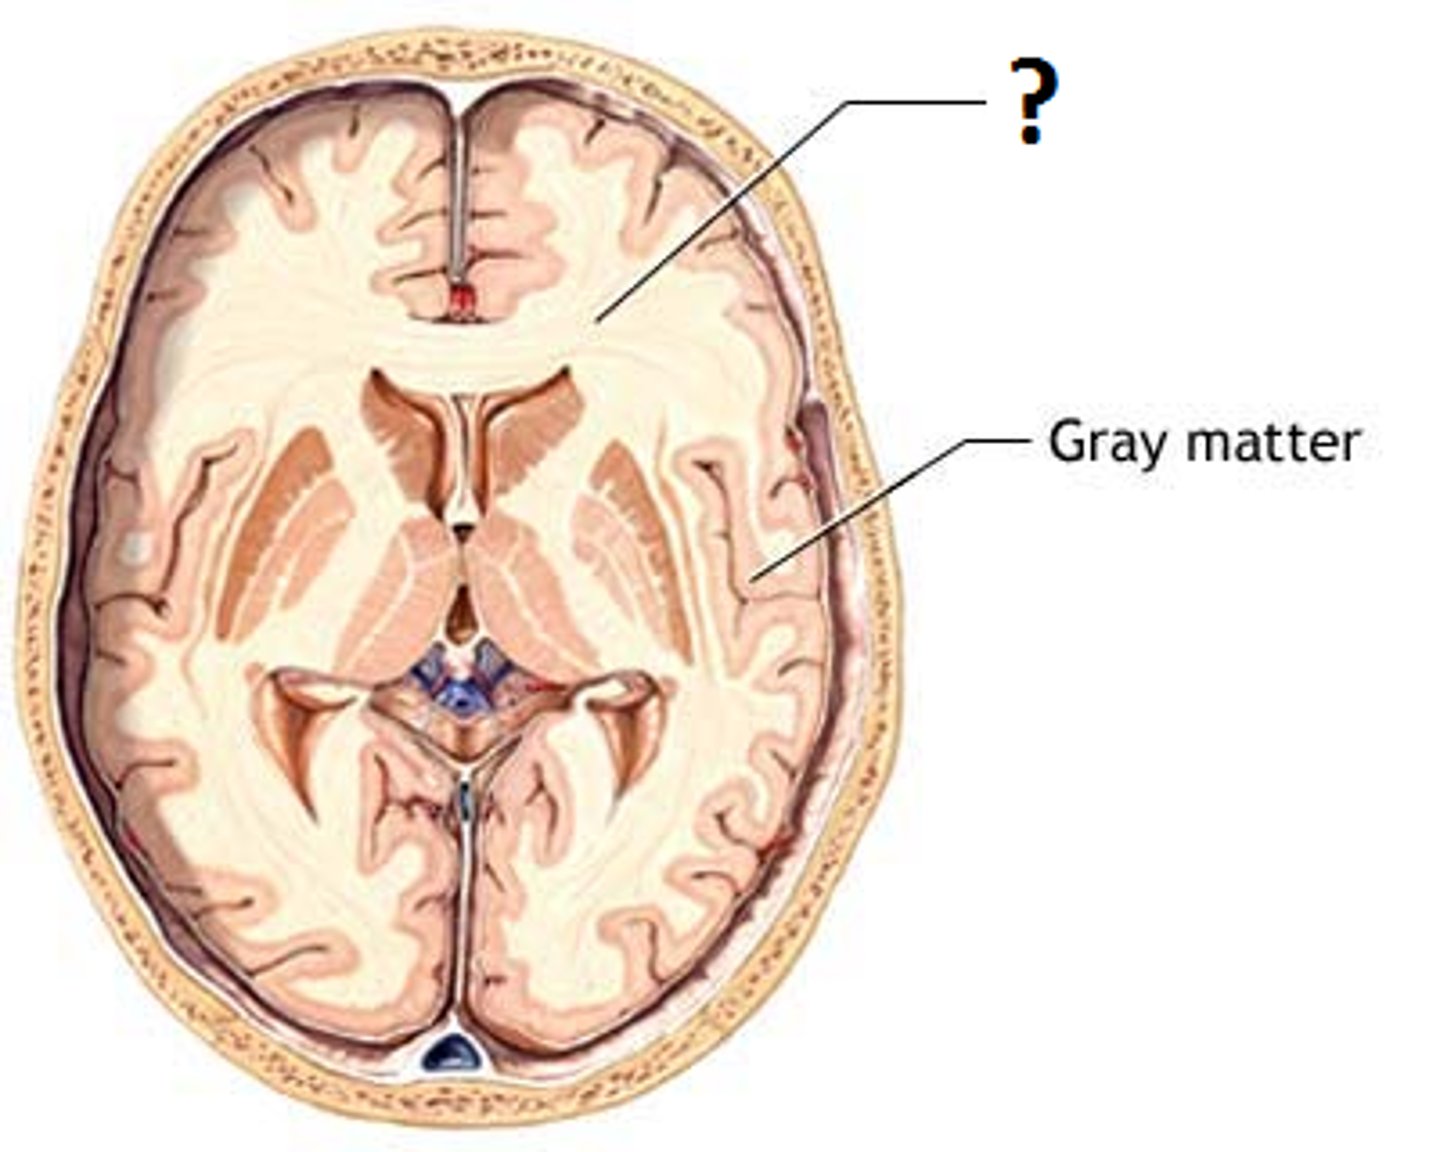

white matter

myelinated axons

commissural tracts of white matter

conducts nerve impulses one cerebral gyri to corresponding gyri in the other cerebral hemisphere.

corpus callosum

broad band of white matter containing axons that extend between the cerebral hemispheres